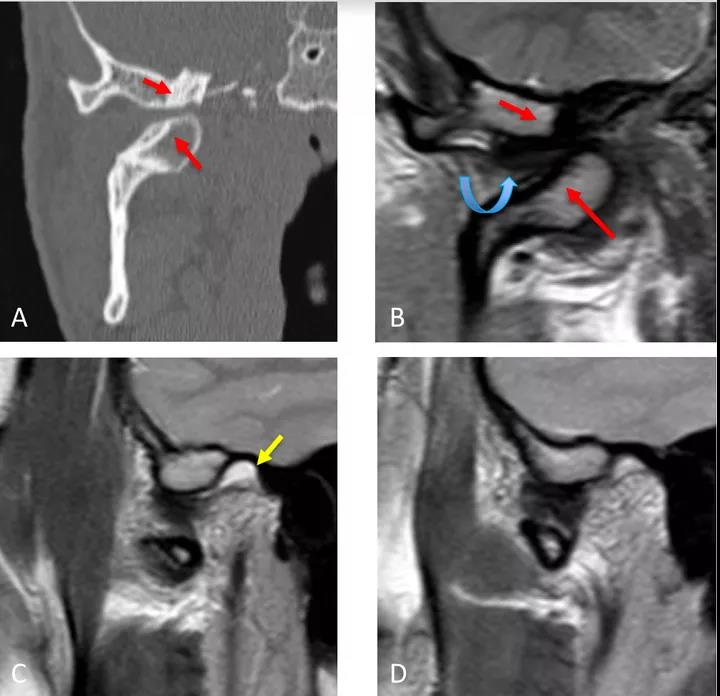

病例二:顳下頜關(guān)節(jié)脫位

冠狀面CT圖(A)和冠狀面PDWI圖(閉口)(B):顯示由于先前骨折導(dǎo)致的下頜髁突內(nèi)側(cè)移位的顳下頜關(guān)節(jié)脫位,與骨折畸形愈合、前上髁和后顳嵴硬化(紅色箭頭)相關(guān)。關(guān)節(jié)盤位于下頜骨髁突和顳突之間,失去正常的形態(tài)(彎曲箭頭)。

矢狀位T2WI圖(閉口)(C):顯示正常位置的下頜骨髁突及關(guān)節(jié)積液(黃色箭頭)。

矢狀位PDWI圖(開(kāi)口)(D)顯示髁突明顯偏移。